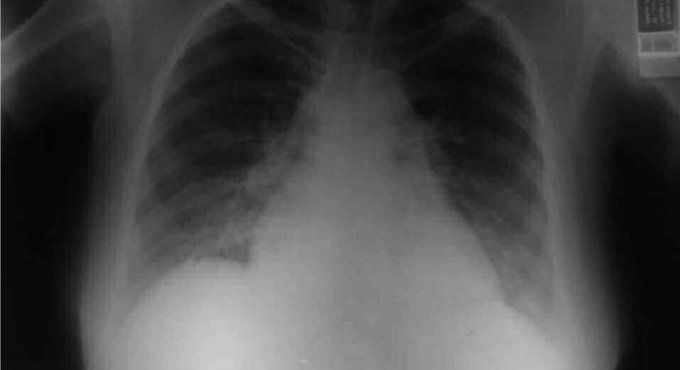

Sağlık Bakanı Fahrettin Koca, 25 Temmuz günü koronavirüs verilerini açıklarken, Kocaeli’ni pnömonili hasta sayısı oranı en çok artan iller arasında saymıştı. Zatüre anlamına gelen pnömonili vakalarındaki artış endişelendirmişi. Bakan Koca’nın bu açıklamasının ardında ise bir skandal ortaya çıktı. Kocaeli’de verilerin eksik girildiği ortaya çıktı. Sağlık Müdürlüğü’nün pnömonili verilerini yanlış girmesi sonrası ise Bakan Kocae böyle bir açıklama yapmak zorunda kalmıştı. İl Sağlık Müdürü Şenol Ergüney ise şunu doktorlara atarak, “1 hafta önce bazı doktorlarımız pnömonil verilerini eksik girmiş. Bunu fark ettik ve düzelttik. Düzeltince de doğal olarak verilerimiz yüksek gözüktü” dedi.Bu skandal olay sonrası ise Kocaeli ile ilgili bilgilerin ne kadar doğru olduğu ise tartışma konusu oldu.

Kocaeli’nin “Pnömonili” verilerini yanlış girmişler!

Sağlık Bakanı Fahrettin Koca’nın geçtiğimiz gün açıkladığı verilerde Kocaeli’nin “Pnömonili” verisi en yüksek çıkan iller arasında sayması sonrası, Sağlık Müdürlüğü’nün verileri yanlış girdiği ortaya çıktı